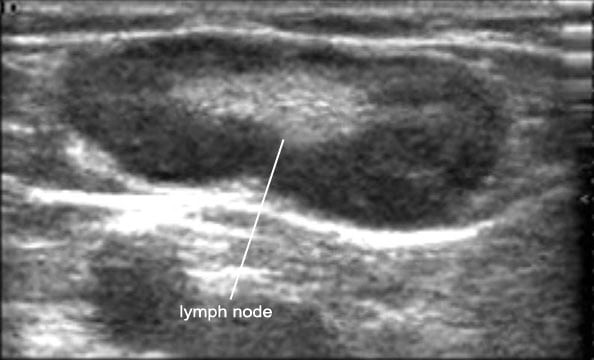

УЗИ лимфоузлов при лимфоме Ходжкина

Раздел: Образы вокруг